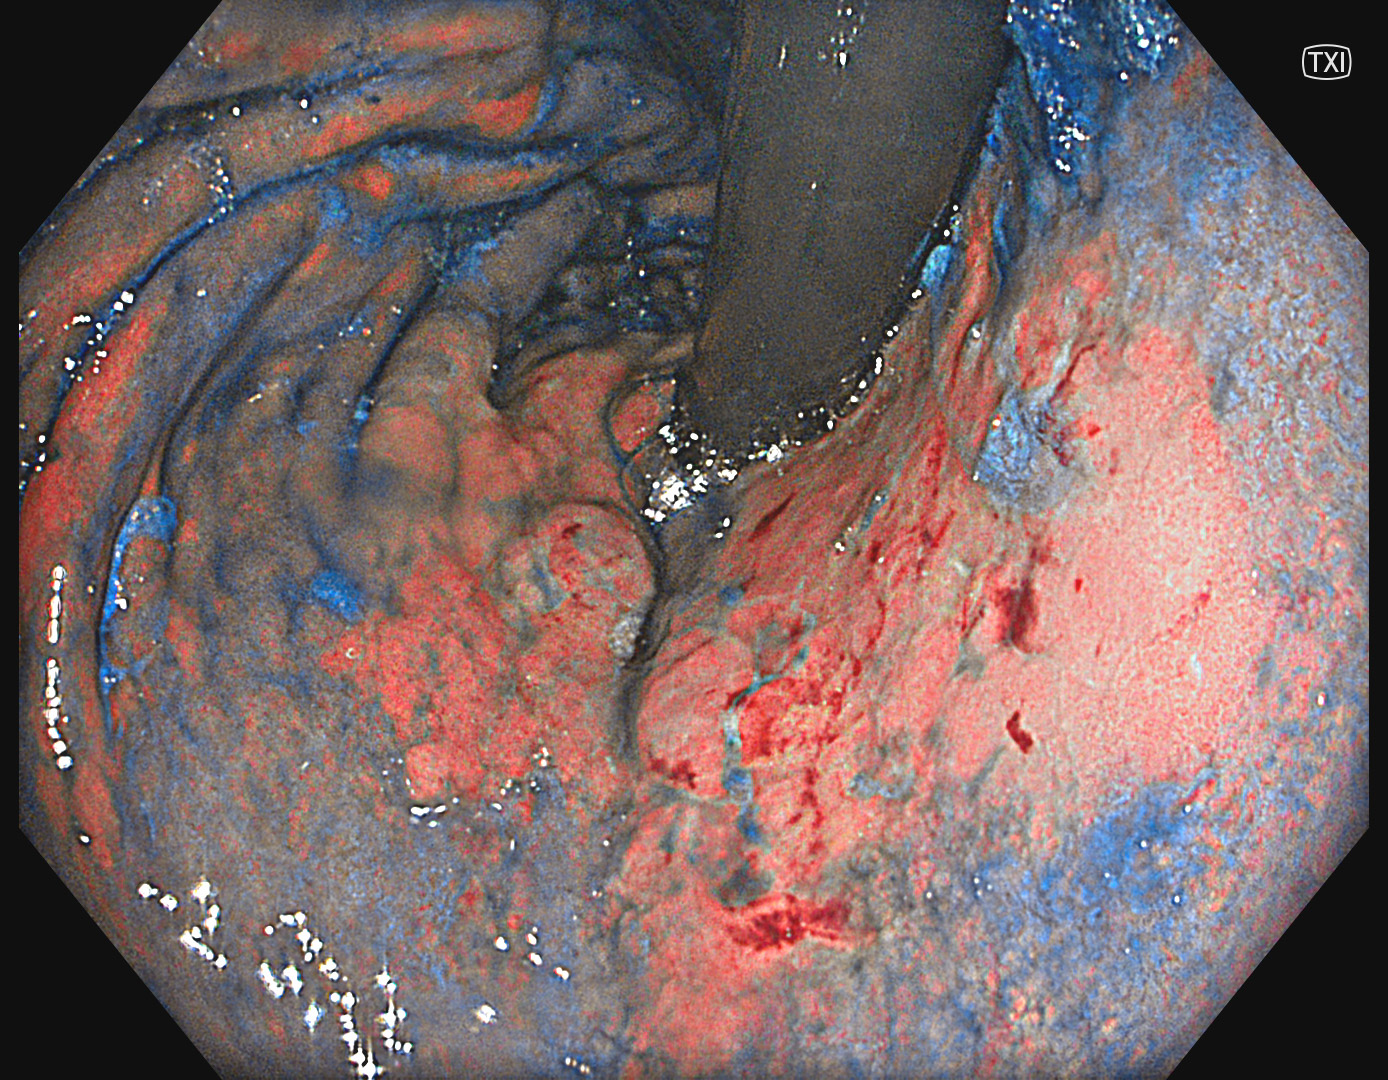

2. TXI

#TXI Mode 1 #A7 structure enhancement #Auto Iris

TXI is enhancing the color contrast and structure between the suspicious area and the surrounding mucosa.

6. TXI with indigocarmine

The extent of the lesion can be nicely identified by TXI in combination with indigocarmine.

The case illustrates the value of TXI in detection and delineation of early gastric carcinomas. Especially the delineation was difficult due to indistinct borders. The combination of TXI and indigocarmine enabled the strong color contrast and delineation of the lesion. NBI remains the first-hand modality for optical diagnosis.